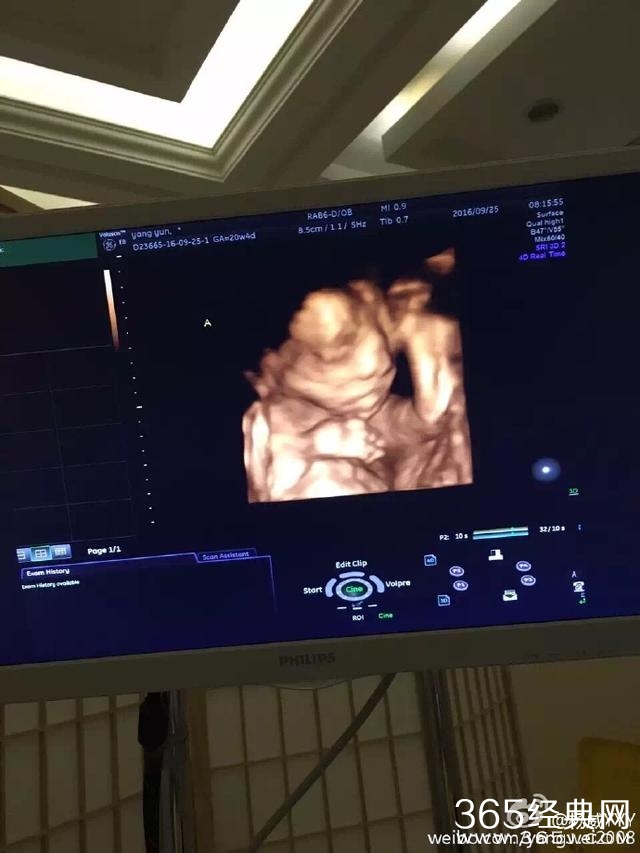

今晚杨威在微博晒出杨云所怀双胞胎的B超照片,并称:“一个像自己,一个像杨云。”暗示怀的是龙凤胎,这幸福秀的简直不要太甜蜜!!看来可爱杨阳洋很快就要有两个可爱的弟弟妹妹了。

可以从照片看出杨云腹中胎儿与杨威五官很像,怀了是龙凤胎,那可就真的满足了杨威的女儿梦啊,要知道女儿控的他之前非常希望能有一个小公主。观众为黄渤贡献了70亿票房,却只投6票给他,输给冯绍峰,心疼